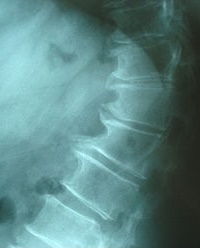

داء الفقار (إنگليزية: Spondylosis)، هو تنكس العمود الفقري لأي سبب. بالمعنى الضيق ، يشير إلى فصال عظامي في العمود الفقري ، وهو تآكل العمود الفقري المرتبط بالعمر ، وهو السبب الأكثر شيوعًا للإصابة بداء الفقار. تؤثر العملية التنكسية في الفصال العظامي بشكل رئيسي على الأجسام الفقرية ، والفوه العصبية ، ومفاصل الوجه ( متلازمة الوجيه ). إذا كانت شديدة ، فقد تسبب ضغطًا على النخاع الشوكي أو جذور الأعصاب مع اضطرابات حسية أو حركية لاحقة ، مثل الألم والتنمل وعدم التوازن وضعف العضلات في الأطراف

عندما تضيق المسافة بين فقرتين متجاورتين ، قد يؤدي ضغط جذر العصب الخارج من النخاع الشوكي إلى اعتلال الجذور (اضطرابات حسية وحركية ، مثل ألم شديد في الرقبة أو الكتف أو الذراع أو الظهر أو الساق ، مصحوبًا بضعف العضلات ). أقل شيوعًا ، قد يؤدي الضغط المباشر على النخاع الشوكي (عادةً في العمود الفقري العنقي) إلى اعتلال النخاع ، الذي يتميز بضعف عام ، وخلل في المشي ، وفقدان التوازن ، وفقدان السيطرة على الأمعاء أو المثانة. قد يعاني المريض من صدمات (تنمل) في اليدين والساقين بسبب ضغط الأعصاب والإقفار . في حالة إصابة فقرات العنق ، يتم تسميتها بداء الفقار الرقبي. يسمى داء الفقار أسفل الظهر داء الفقار القطني. المصطلح مشتق من اليونانية القديمة σπόνδυλος spóndylos ، "فقرة" ، في صيغة الجمع "فقرات - العمود الفقري".